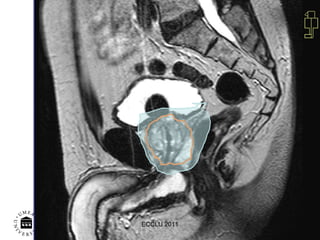

Dose plan  ECCLU 2011

Rectum and dose distribution

Rectum and dosedistribution